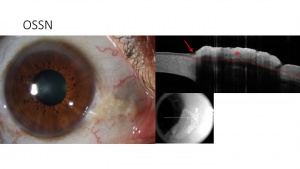

Ocular surface squamous neoplasia (OSSN) - epithelial

Ocular surface squamous neoplasia (OSSN) has proven to be distinctive on AS-OCT. Notably, OSSN is an epithelial lesion, both on the cornea and on the conjunctiva. Distinctive AS-OCT features including 1. thickened epithelium; 2. hyperreflective epithelial layer; and 3. an abrupt transition from normal to abnormal epithelium. AS-OCT features resolve completely with normalization of the epithelium after successful medical therapy or surgical intervention. Using a cut off of approximately 140 um, AS-OCT findings have a 94-100% sensitivity and 100% specificity for the diagnosis of OSSN. AS-OCT can also be used to detect subclinical disease that often is not appreciated on slit-lamp examination. As such, AS-OCT serves as a powerful tool for the non-invasive diagnosis of OSSN and can be used to determine need for treatment initiation as well as monitoring of the disease course. [1][5][9](Figure 3)